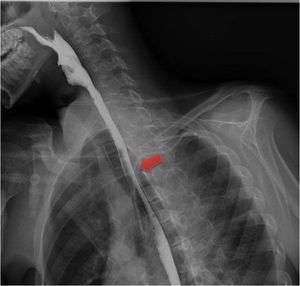

A 20-year-old man presented with chest pain and fever. Computed tomography of the chest showed a fusiform paravertebral mass measuring 27 × 30 × 100 mm indicative of a superinfected collection (Fig. 1). An oesophageal transit study with Gastrografin® ruled out perforation (Fig. 2). A decision was made to administer antibiotic therapy and perform a surgical examination given the evidence of superinfection. Intraoperative oesophagogastroduodenoscopy revealed, 30−36 cm from the dental arch, whitish oesophageal mucosa with haemorrhagic suffusion, a mass effect and two orifices draining a purulent fluid (Fig. 3). Right lateral thoracoscopy revealed thickening of the oesophageal wall, with no evidence of cyst formation. On subsequent imaging tests, the collection was seen to gradually shrink and then disappear. Oesophageal biopsies in follow-up oesophagogastroduodenoscopy yielded no histological findings.

Oesophageal intramural dissection consists of laceration of the mucosa, resulting in longitudinal dissection that separates the mucosa from the submucosa.1,2 In a contained perforation, the muscle layer remains intact.1–3 Microorganisms can breach the lacerated mucosa and complicate the situation with an intramural oesophageal abscess.1 This finding is rare and usually iatrogenic in patients on anticoagulation therapy.1,2 However, we have reported an idiopathic case in a young patient with no history of endoscopic manipulation, vomiting or trauma. Imaging tests may show a double-lumen oesophagus or, as in this case, a hypodense paraoesophageal collection.1